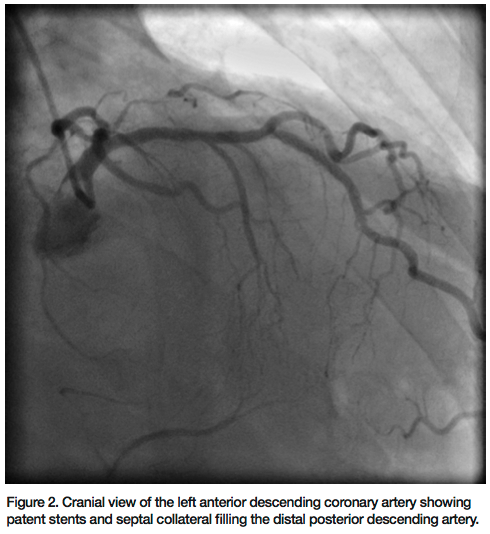

Percutaneous intervention of the RCA was performed via the right radial approach using a 6 French (Fr) MAC 3.0 guide catheter (Medtronic). A 300 cm Kinetix wire (Boston Scientific) and subsequently a hydrophilic PT II Graphix (Boston Scientific) wire along with a 1.25mm x 10mm over-the-wire balloon were used to cross the CTO (Figure 3). After the initial crossing into the proximal cap, we could not advance the wire further. With the hope of creating a channel through the proximal cap, a 0.9 laser catheter (Spectranetics

Corporation) was used. The laser softened the cap and allowed us to cross through the entire segment of the CTO with a Kinetix wire. Further lasing was performed at 80 Hertz pulse fluency and at 80 mJ/mm2 repetition cycle for debulking of the entire in-stent occlusion area (Figure 4). A 2.75mm balloon was utilized to pre-dilate the whole length of the CTO. Intravascular ultrasound (IVUS) was performed. Multiple overlapping Ion drug-eluting stents (Boston Scientific) were deployed to the RCA (Figure 5) and post dilated to 3.00 mm, demonstrating excellent angiographic results and TIMI-III flow (Figure 6). The sheath was removed and a hemostatic band was applied for two hours. The patient was discharged the next morning on prasugrel and aspirin along with other medications.